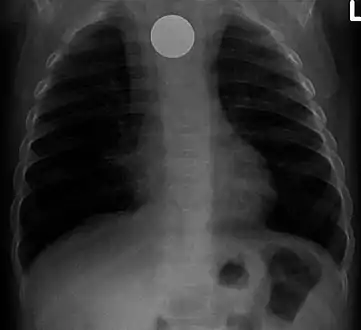

A coin seen on AP CXR in the esophagus